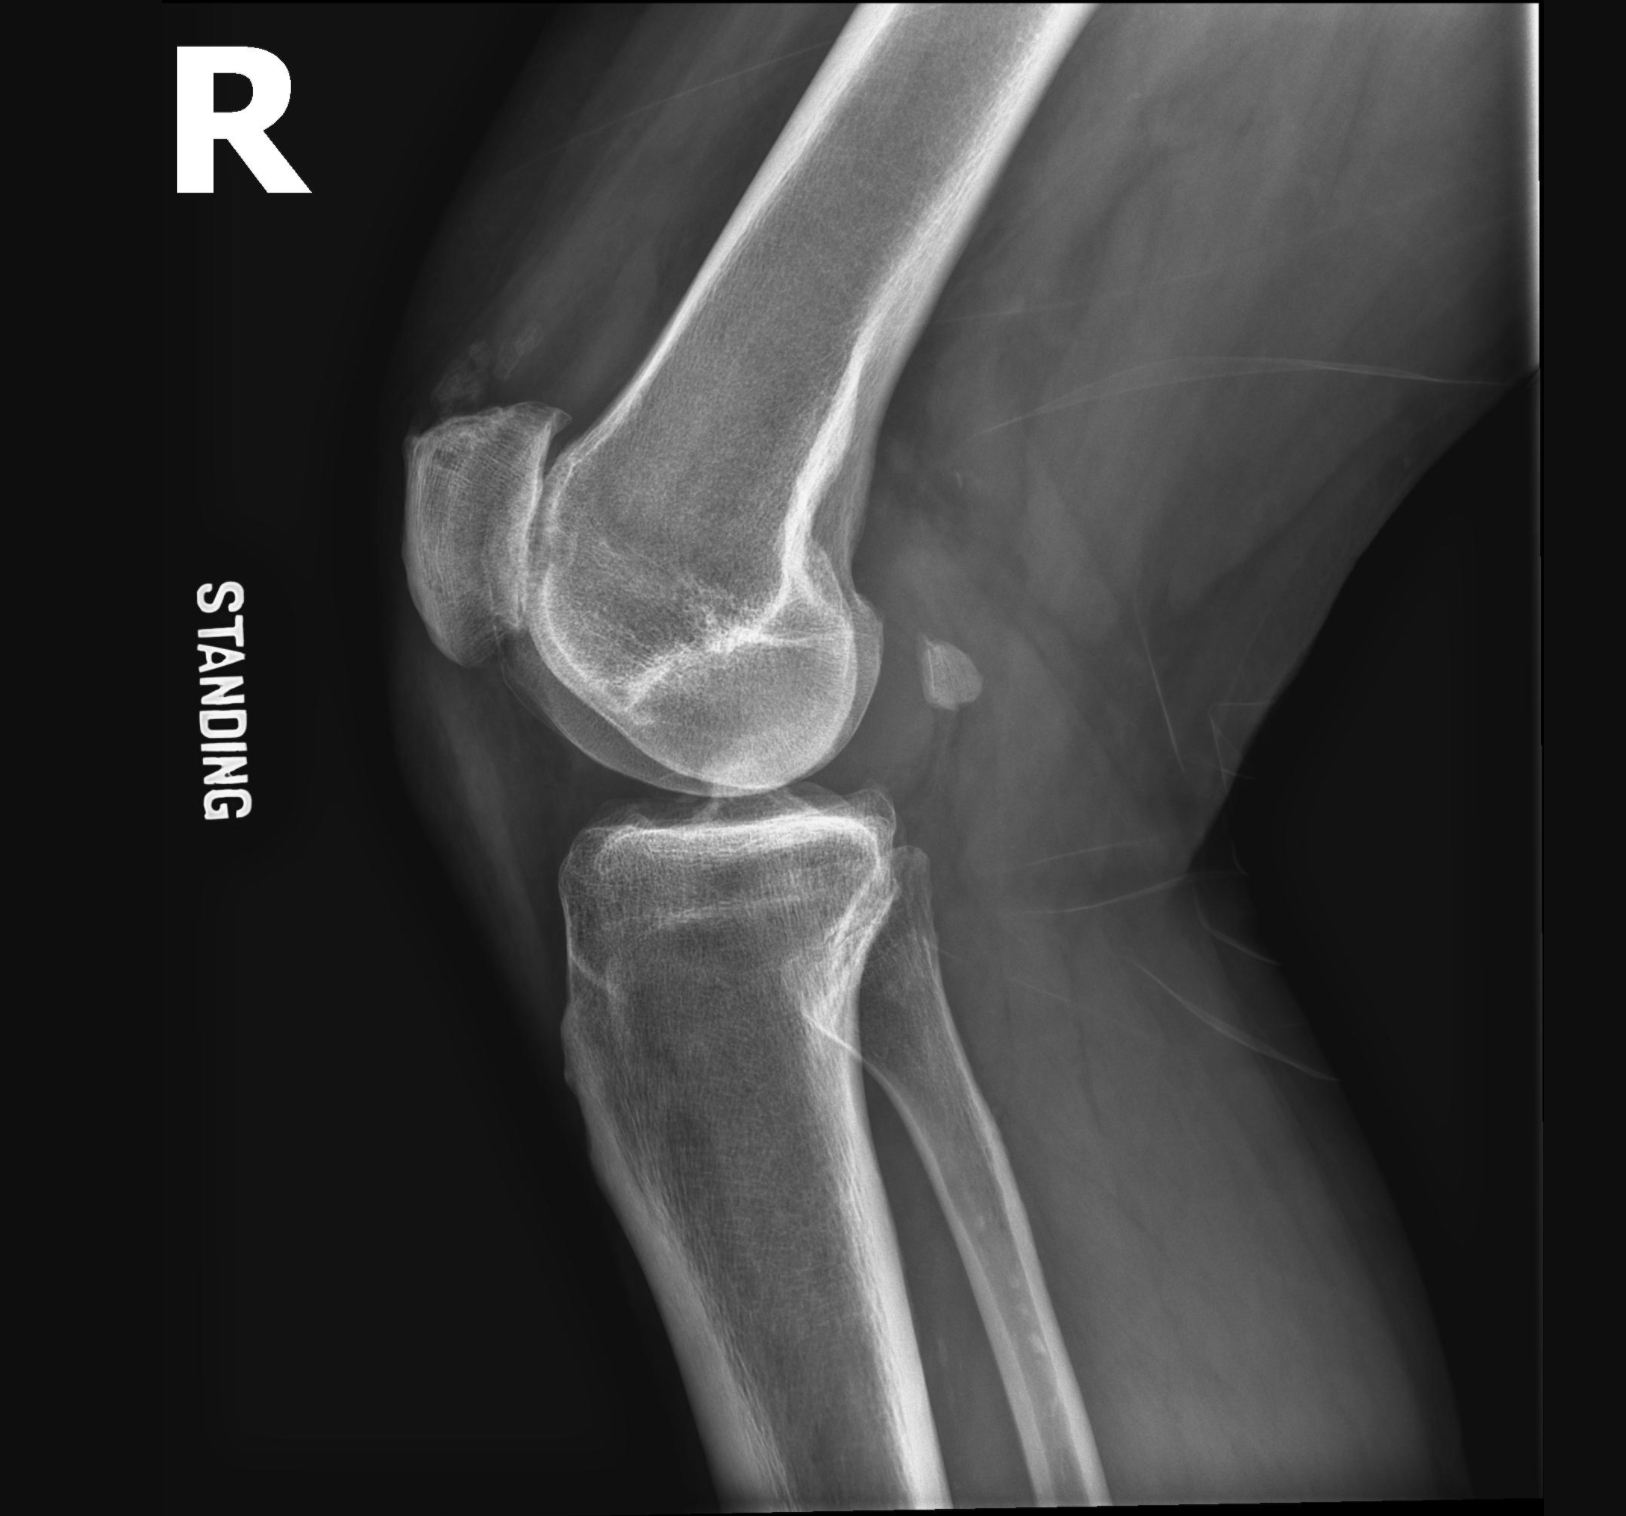

Physical exam demonstrates 0-110 degree range of motion of the right knee, tenderness and a small effusion of the right knee without warmth or erythema. No obvious skin pigment changes or brown-colored skin changes symmetrically on the cheeks typically seen with exogenous Ochronosis. He is 6 feet tall and 250 pounds. Preoperative x-rays and MRI are shown in Figures 1-10.